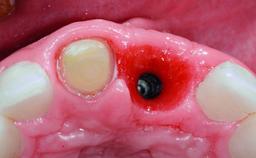

A 32-year-old female Caucasian patient with a compromised maxillary right central incisor was referred to us by a general dentist. Her chief complaints were discomfort and mobility of tooth 11 with unsatisfactory esthetics due to discoloration. The patient reported a previous trauma, some years earlier, as the origin of pathology on the afflicted tooth. Anamnesis was negative for any other dental or periodontal pathology in the remaining dentition. The patient did not take any medication and reported to be a light smoker (5–10 cigs/day). She had high esthetic expectations of her treatment. The extraoral examination revealed a high smile line with full exposure of her maxillary teeth and surrounding soft tissue in the area between the second premolars.

| # of Implants | 1 |

| Type of Implants | Reduced-Diameter|Two-Piece |